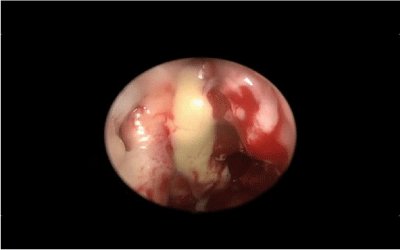

9. So it was facilitated the drainage of mucus-pus nasally by the help of the second operator who performed repeated maneuvers of eye’s pressure (Figure 5).

Figure 5 Nasally drainage of mucus-pus.